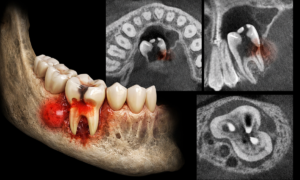

C. CBCT (Cone Beam Computed Tomography)

This is the gold standard for complex cases. A standard X-ray is 2-dimensional (flat), but your tooth is 3-dimensional.

1. Purpose: A CBCT scan allows us to slice the image layer by layer. We can see exactly how big the Cavity Abscess is, which direction it is spreading, and if there are hidden “accessory” canals in the root that a normal X-ray missed.

2. When It Is Required:

a. Failed Root Canals (Re-treatment).

b. Multi-rooted teeth (Molars) where roots overlap.

c. Planning for Dental Implants after extracting an infected tooth.